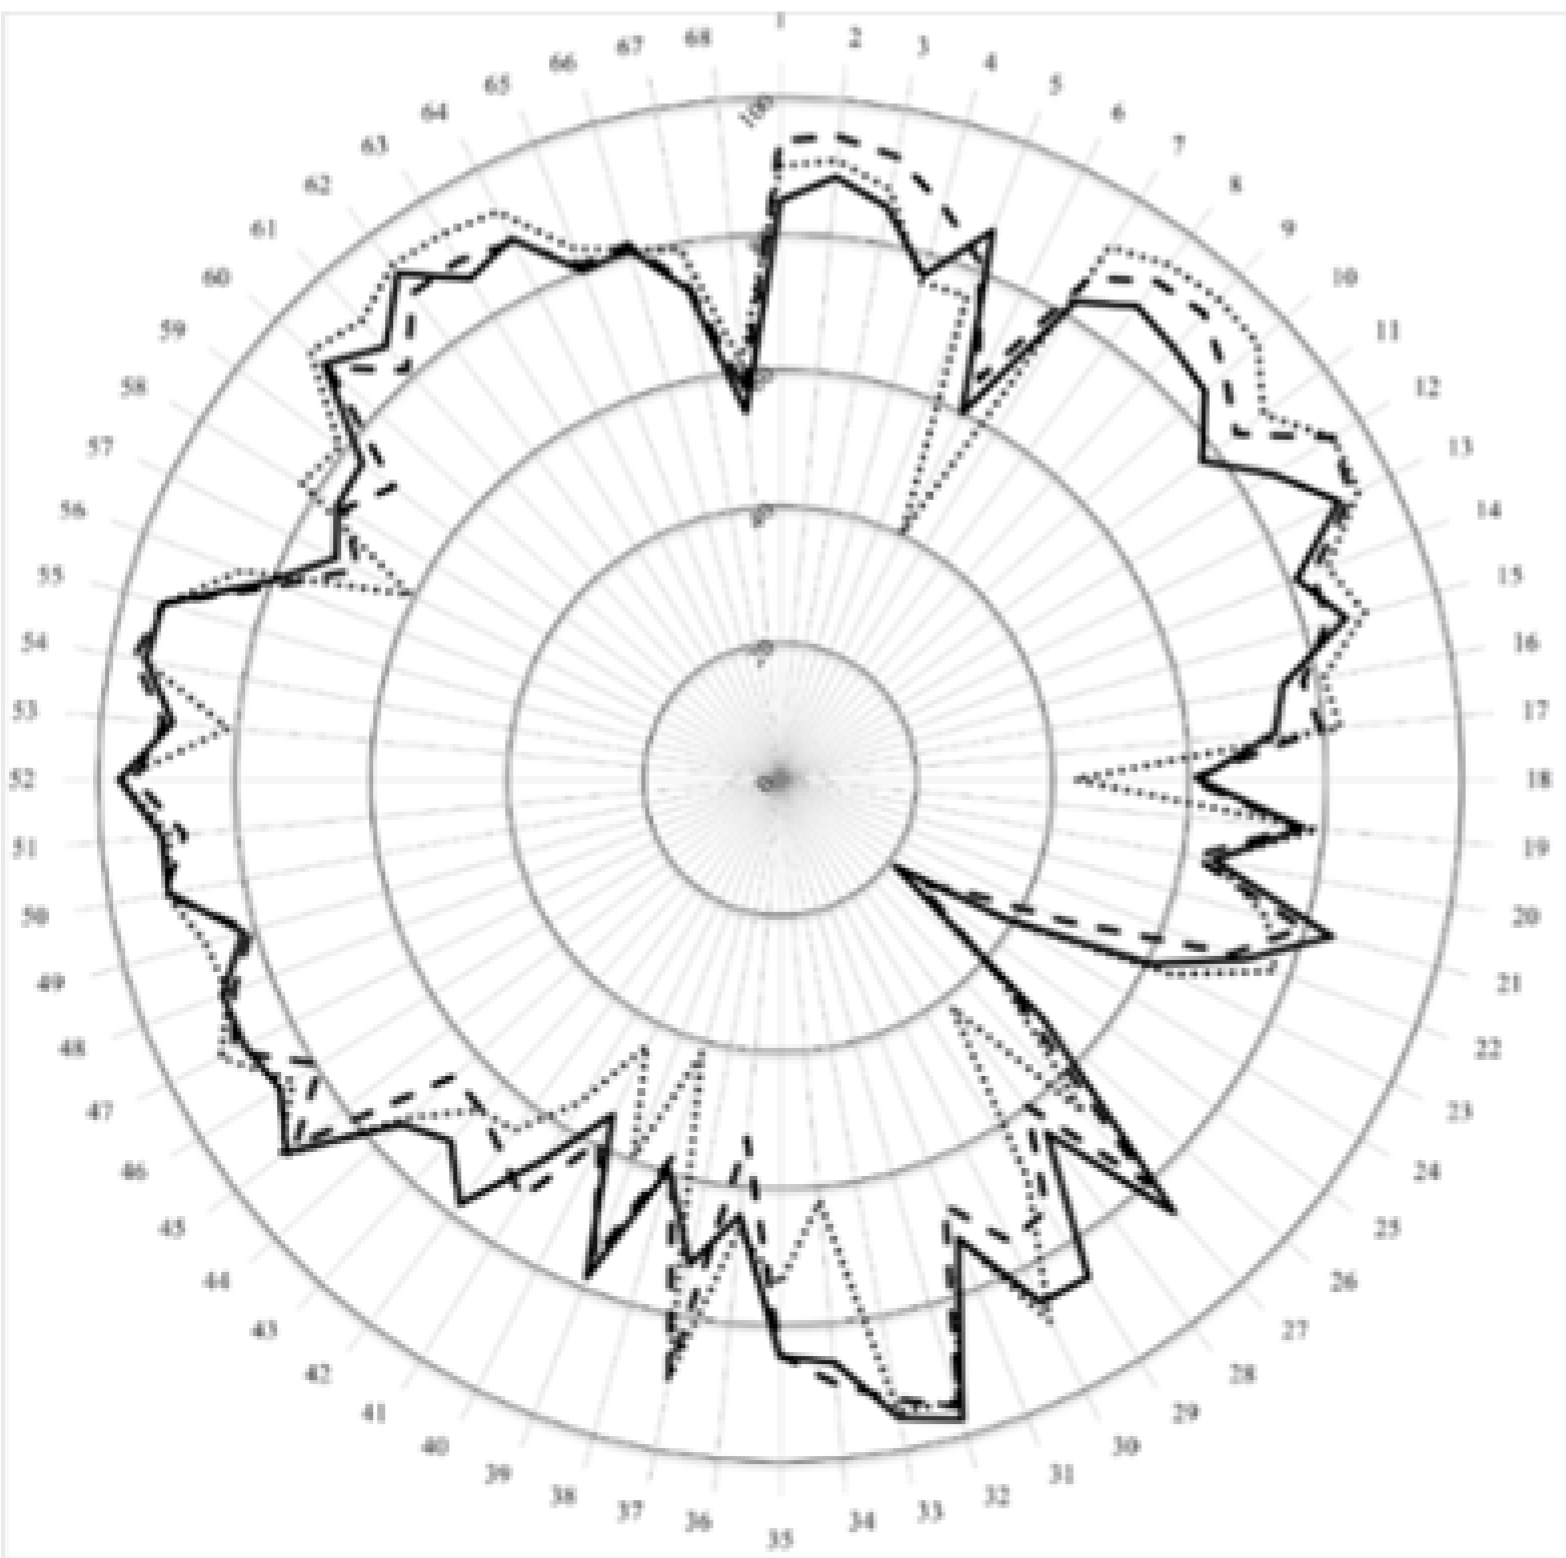

3. Results and Discussion

| Cluster 7. Personal competences: learning and knowledge. | 1 | Ability to identify learning needs and to learn independently (including continuous professional development (CPD)). | 84.5 | 93.7 | 15.7 | 89.8 | 13.1 |

| 2 | Analysis: ability to apply logic to problem solving, evaluating pros and cons and following up on the solution found. | 88.8 | 94.5 | 7.5 | 91.1 | 3.6 | |

| 3 | Synthesis: capacity to gather and critically appraise relevant knowledge and to summarise the key points. | 85.1 | 92.8 | 10.8 | 87.9 | 4.0 | |

| 4 | Capacity to evaluate scientific data in line with current scientific and technological knowledge. | 76.5 | 87.3 | 18.5 | 75.8 | 0.4 | |

| 5 | Ability to interpret preclinical and clinical evidence-based medical science and apply the knowledge to pharmaceutical practice. | 86.0 | 81.2 | 5.2 | 75.9 | 17.3 | |

| 6 | Ability to design and conduct research using appropriate methodology. | 60.6 | 65.4 | 4.9 | 40.2 | 34.3 | |

| 7 | Ability to maintain current knowledge of relevant legislation and codes of pharmacy practice. | 81.7 | 86.3 | 3.3 | 91.7 | 25.7 | |

| Cluster 8. Personal competences: values. | 8 | Demonstrate a professional approach to tasks and human relations. | 86.6 | 91.5 | 7.7 | 94.5 | 23.3 |

| 9 | Demonstrate the ability to maintain confidentiality. | 85.4 | 92.3 | 22.8 | 95.3 | 50.6 | |

| 10 | Take full personal responsibility for patient care and other aspects of one’s practice. | 84.4 | 88.3 | 3.2 | 94.8 | 24.9 | |

| 11 | Inspire the confidence of others in one’s actions and advice. | 77.8 | 83.8 | 8.9 | 88.8 | 13.0 | |

| 12 | Demonstrate high ethical standards. | 85.3 | 95.3 | 43.4 | 95.2 | 24.6 | |

| Cluster 9. Personal competences: communication and organisational skills. | 13 | Effective communication skills (both orally and written). | 91.2 | 93.5 | 3.9 | 94.8 | 4.0 |

| 14 | Effective use of information technology. | 81.1 | 83.8 | 1.4 | 86.1 | 3.8 | |

| 15 | Ability to work effectively as part of a tea. | 86.4 | 83.3 | 6.1 | 89.2 | 1.1 | |

| 16 | Ability to identify and implement legal and professional requirements relating to employment (e.g., for pharmacy technicians) and to safety in the workplace. | 74.8 | 77.9 | 1.9 | 81.0 | 4.5 | |

| 17 | Ability to contribute to the learning and training of staff. | 73.5 | 79.6 | 6.6 | 82.5 | 6.6 | |

| 18 | Ability to design and manage the development processes in the production of medicines. | 61.2 | 60.0 | 0.8 | 43.2 | 38.0 | |

| 19 | Ability to identify and manage risk and quality of service issues. | 77.5 | 76.1 | 4.0 | 79.2 | 2.3 | |

| 20 | Ability to identify the need for new services. | 65.0 | 61.8 | 7.7 | 64.5 | 1.2 | |

| 21 | Ability to communicate in English and/or locally relevant languages. | 84.5 | 79.6 | 2.3 | 74.1 | 16.3 | |

| 22 | Ability to evaluate issues related to quality of service. | 73.0 | 71.0 | 3.5 | 77.9 | 7.4 | |

| 23 | Ability to negotiate, understand a business environment and develop entrepreneurship. | 62.2 | 46.4 | 15.6 | 64.1 | 2.0 | |

| Cluster 10. Personal competences: knowledge of different areas of the science of medicines. | 24 | Plant and animal biology. | 38.8 | 31.1 | 5.1 | 39.3 | 1.0 |

| 25 | Physics. | 20.9 | 25.6 | 2.3 | 21.7 | 0.8 | |

| 26 | General and inorganic chemistry | 53.0 | 45.6 | 3.3 | 43.9 | 5.3 | |

| 27 | Organic and medicinal/pharmaceutical chemistry. | 86.3 | 80.2 | 10.8 | 66.0 | 37.0 | |

| 28 | Analytical chemistry | 65.8 | 60.0 | 3.0 | 41.9 | 46.9 | |

| 29 | General and applied biochemistry (medicinal and clinical). | 85.4 | 74.2 | 10.8 | 68.8 | 22.6 | |

| 30 | Anatomy and physiology; medical terminology. | 85.2 | 75.8 | 11.2 | 88.7 | 3.3 | |

| 31 | Microbiology. | 72.2 | 67.0 | 3.3 | 72.2 | 1.5 | |

| 32 | Pharmacology including pharmacokinetics. | 97.5 | 95.6 | 3.7 | 94.7 | 3.0 | |

| 33 | Pharmacotherapy and pharmaco-epidemiology. | 95.3 | 92.5 | 3.1 | 94.3 | 2.2 | |

| 34 | Pharmaceutical technology including analyses of medicinal products. | 86.9 | 89.0 | 1.4 | 62.0 | 50.8 | |

| 35 | Toxicology. | 85.0 | 84.4 | 17.3 | 74.0 | 27.7 | |

| 36 | Pharmacognosy. | 65.9 | 52.9 | 11.3 | 66.5 | 2.1 | |

| 37 | Legislation and professional ethics. | 71.7 | 88.8 | 26.8 | 89.5 | 44.2 | |

| Cluster 11. Personal competences: understanding of industrial pharmacy. | 38 | Current knowledge of design, synthesis, isolation, characterisation and biological evaluation of active substances. | 59.9 | 57.5 | 1.9 | 41.7 | 34.2 |

| 39 | Current knowledge of good manufacturing practice (GMP) and of good laboratory practice (GLP). | 79.2 | 75.4 | 1.6 | 59.4 | 29.8 | |

| 40 | Current knowledge of European directives on qualified persons (QPs). | 55.3 | 59.2 | 1.8 | 43.7 | 39.9 | |

| 41 | Current knowledge of drug registration, licensing and marketing. | 65.7 | 72.1 | 4.6 | 55.7 | 11.9 | |

| 42 | Current knowledge of good clinical practice (GCP). | 78.1 | 68.2 | 9.1 | 64.5 | 23.8 | |

| Cluster 12. Patient care competences: patient consultation and assessment. | 43 | Ability to perform and interpret medical laboratory tests. | 72.0 | 65.3 | 5.9 | 65.5 | 6.0 |

| 44 | Ability to perform appropriate diagnostic or physiological tests to inform clinical decision making e.g., measurement of blood pressure. | 76.1 | 64.5 | 17.3 | 73.6 | 7.8 | |

| 45 | Ability to recognise when referral to another member of the healthcare team is needed because a potential clinical problem is identified (pharmaceutical, medical, psychological or social). | 91.7 | 89.1 | 2.2 | 91.7 | 9.5 | |

| Cluster 13. Patient care competences: need for drug treatment. | 46 | Retrieval and interpretation of relevant information on the patient’s clinical background. | 85.6 | 79.3 | 8.4 | 84.0 | 0.7 |

| 47 | Retrieval and interpretation of an accurate and comprehensive drug history if and when required. | 87.6 | 89.4 | 5.1 | 91.5 | 2.3 | |

| 48 | Identification of non-adherence and implementation of appropriate patient intervention. | 87.1 | 85.8 | 6.1 | 86.8 | 24.5 | |

| 49 | Ability to advise to physicians and—in some cases—prescribe medication. | 81.9 | 80.7 | 2.5 | 87.6 | 5.3 | |

| Cluster 14. Patient care competences: drug interactions. | 50 | Identification, understanding and prioritisation of drug-drug interactions at a molecular level (e.g., use of codeine with paracetamol). | 91.4 | 91.8 | 1.1 | 91.6 | 0.6 |

| 51 | Identification, understanding, and prioritisation of drug-patient interactions, including those that preclude or require the use of a specific drug (e.g., trastuzumab for treatment of breast cancer in women with HER2 overexpression). | 91.4 | 87.7 | 4.4 | 89.7 | 5.0 | |

| 52 | Identification, understanding, and prioritisation of drug-disease interactions (e.g., NSAIDs in heart failure). | 97.0 | 94.5 | 8.9 | 96.6 | 2.7 | |

| Cluster 15. Patient care competences: provision of drug product. | 53 | Familiarity with the bio-pharmaceutical, pharmacodynamic and pharmacokinetic activity of a substance in the body. | 89.3 | 90.8 | 3.5 | 81.2 | 11.6 |

| 54 | Supply of appropriate medicines taking into account dose, correct formulation, concentration, administration route and timing. | 94.3 | 96.3 | 16.3 | 94.9 | 18.0 | |

| 55 | Critical evaluation of the prescription to ensure that it is clinically appropriate and legal. | 93.9 | 94.1 | 6.6 | 94.0 | 11.1 | |

| 56 | Familiarity with the supply chain of medicines and the ability to ensure timely flow of drug products to the patient. | 81.6 | 78.6 | 4.5 | 84.6 | 11.3 | |

| 57 | Ability to manufacture medicinal products that are not commercially available. | 74.1 | 69.0 | 1.5 | 60.5 | 21.2 | |

| Cluster 16. Patient care competences: patient education. | 58 | Promotion of public health in collaboration with other actors in the healthcare system. | 75.8 | 75.1 | 1.1 | 82.6 | 5.9 |

| 59 | Provision of appropriate lifestyle advice on smoking, obesity, etc. | 76.9 | 71.0 | 3.8 | 80.9 | 4.7 | |

| 60 | Provision of appropriate advice on resistance to antibiotics and similar public health issues. | 90.3 | 89.4 | 5.2 | 93.1 | 3.6 | |

| Cluster 17. Patient care competences: provision of information and service. | 61 | Ability to use effective consultations to identify the patient’s need for information. | 85.6 | 81.1 | 3.1 | 90.9 | 11.1 |

| 62 | Provision of accurate and appropriate information on prescription medicines. | 92.7 | 89.3 | 8.0 | 94.4 | 11.0 | |

| 63 | Provision of informed support for patients in selection and use of non-prescription medicines for minor ailments (e.g., cough remedies). | 85.7 | 89.4 | 1.7 | 94.0 | 14.4 | |

| Cluster 18. Patient care competences: monitoring of drug therapy. | 64 | Identification and prioritisation of problems in the management of medicines in a timely manner and with sufficient efficacy to ensure patient safety. | 88.5 | 87.9 | 8.2 | 93.0 | 8.7 |

| 65 | Ability to monitor and report to all concerned in a timely manner, and in accordance with current regulatory guidelines on Good Pharmacovigilance Practices (GVPs), Adverse Drug Events and Reactions (ADEs and ADRs). | 79.8 | 80.9 | 5.0 | 83.4 | 3.3 | |

| 66 | Undertaking of a critical evaluation of prescribed medicines to confirm that current clinical guidelines are appropriately applied. | 80.7 | 81.6 | 0.3 | 80.6 | 4.5 | |

| Cluster 19. Patient care competences: evaluation of outcomes. | 67 | Assessment of outcomes on the monitoring of patient care and follow-up interventions. | 73.3 | 73.7 | 0.5 | 79.0 | 4.4 |

| 68 | Evaluation of cost effectiveness of treatment. | 53.3 | 57.7 | 2.1 | 61.2 | 4.8 |